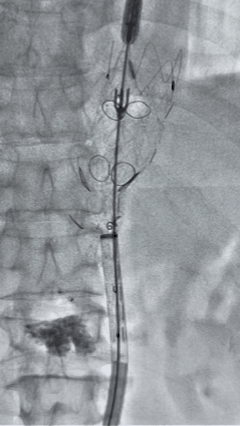

手术过程

1. 患者平卧位,麻醉成功后,留置导尿,常规术野消毒铺巾。左侧肘部切开,暴露左侧肱动脉,置入6F鞘。双侧股动脉穿刺,分别置入10F鞘,全身肝素化。

2. 左侧肱动脉入路,超选至降主动脉,更换8F-900mm长鞘,造影提示IV型胸腹主动脉瘤,累及双肾动脉。

compressed_1770972515230.gif

3. 经右股动脉导入超硬导丝,然后导入先健G-Branch 胸腹主动脉主体覆膜支架TAAA3418120e7i1010 一枚,释放主体支架至内分支打开,然后经左侧肱动脉入路,抓捕预置导丝成功后,将长鞘进入内分支出口处。

2.gif